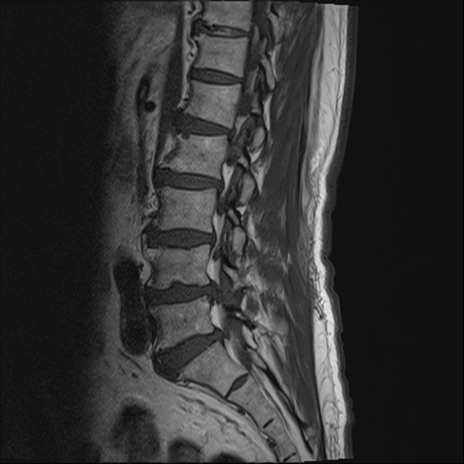

【整形】TIPS症例2 腰椎MRI T1WI(矢状断像)

【症例】70歳代男性

【主訴】左下肢痛

【現病歴】2週間前くらいから腰痛、左下肢痛あり。左臀部から大腿、下腿外側のしびれが常時ある。歩行とともに同部位の痛みあり。

【身体所見】Lasegue70-/60+、Bragard-/±、PTR ±/±、ATR -/-、IP 5/5、TA 5/4、TS 5/5、EHL 右第1足趾なし/3、FHL 5/5、hypersthesia(-)、足背動脈触知良好

異常所見と診断は?